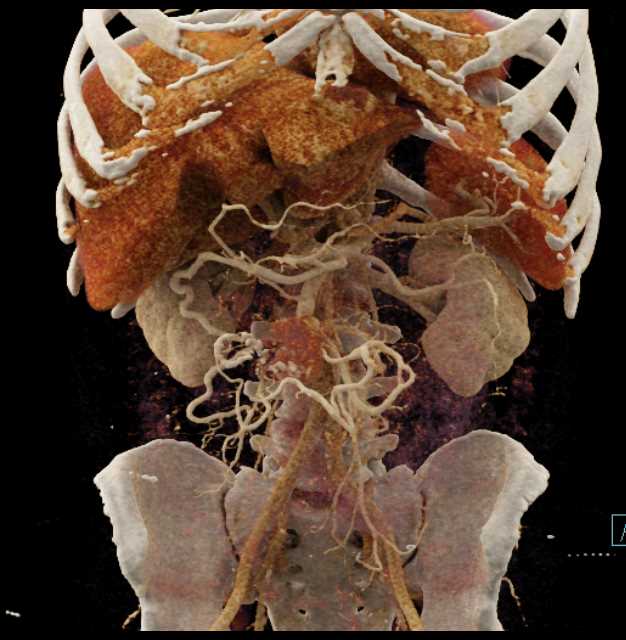

Carcinoid Tumor with Desmoplastic Reaction